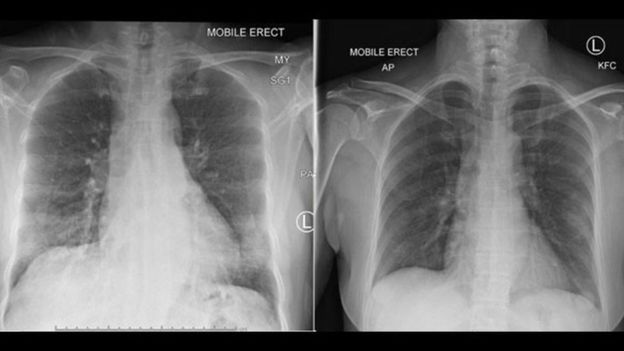

Снимки легких показывают, как они очищаются от инфекции по мере появления иммунных клеток. Правообладатель иллюстрации: PETER DOHERTY INSTITUTE